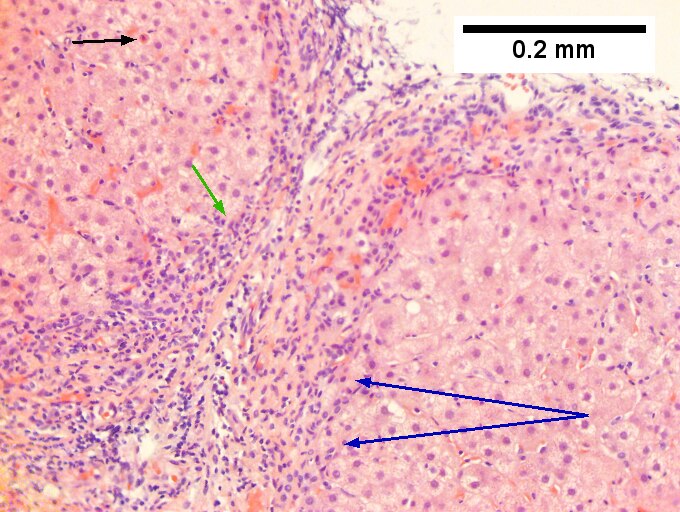

Hepatitis C virus. Metavir activity index 3. Metavir fibrosis stage 1. A. Two dark expanded triads (arrows) have fuzzy edges. B. A triad shows interface hepatitis by lymphocytes and macrophages, with surrounding of hepatocytes (black arrows), piecemeal necrosis, with collections in the lobule (green arrows), spotty necrosis. The portal triad, venule and artery (blue arrows) are unaffected. The central vein’s being near the triad with a small pink line (yellow arrows) indicates significant collapse. C. Reticulin. Thick black lines between triad and central vein (blue arrows) document significant necrosis (LN 2). Two-three cell thick cords (green arrows) show regeneration. D. Reticulin. Thick black lines extending from triad, but not to a central vein, (blue arrows) are not as significant. Black lines surrounding multiple hepatocytes (green arrows) indicate moderate piecemeal necrosis (PMN 2), not severe because it does not involve most of the triad of most triads. E. Trichrome. Only fibrosis of portal triads was seen, indicating metavir fibrosis stage 1.